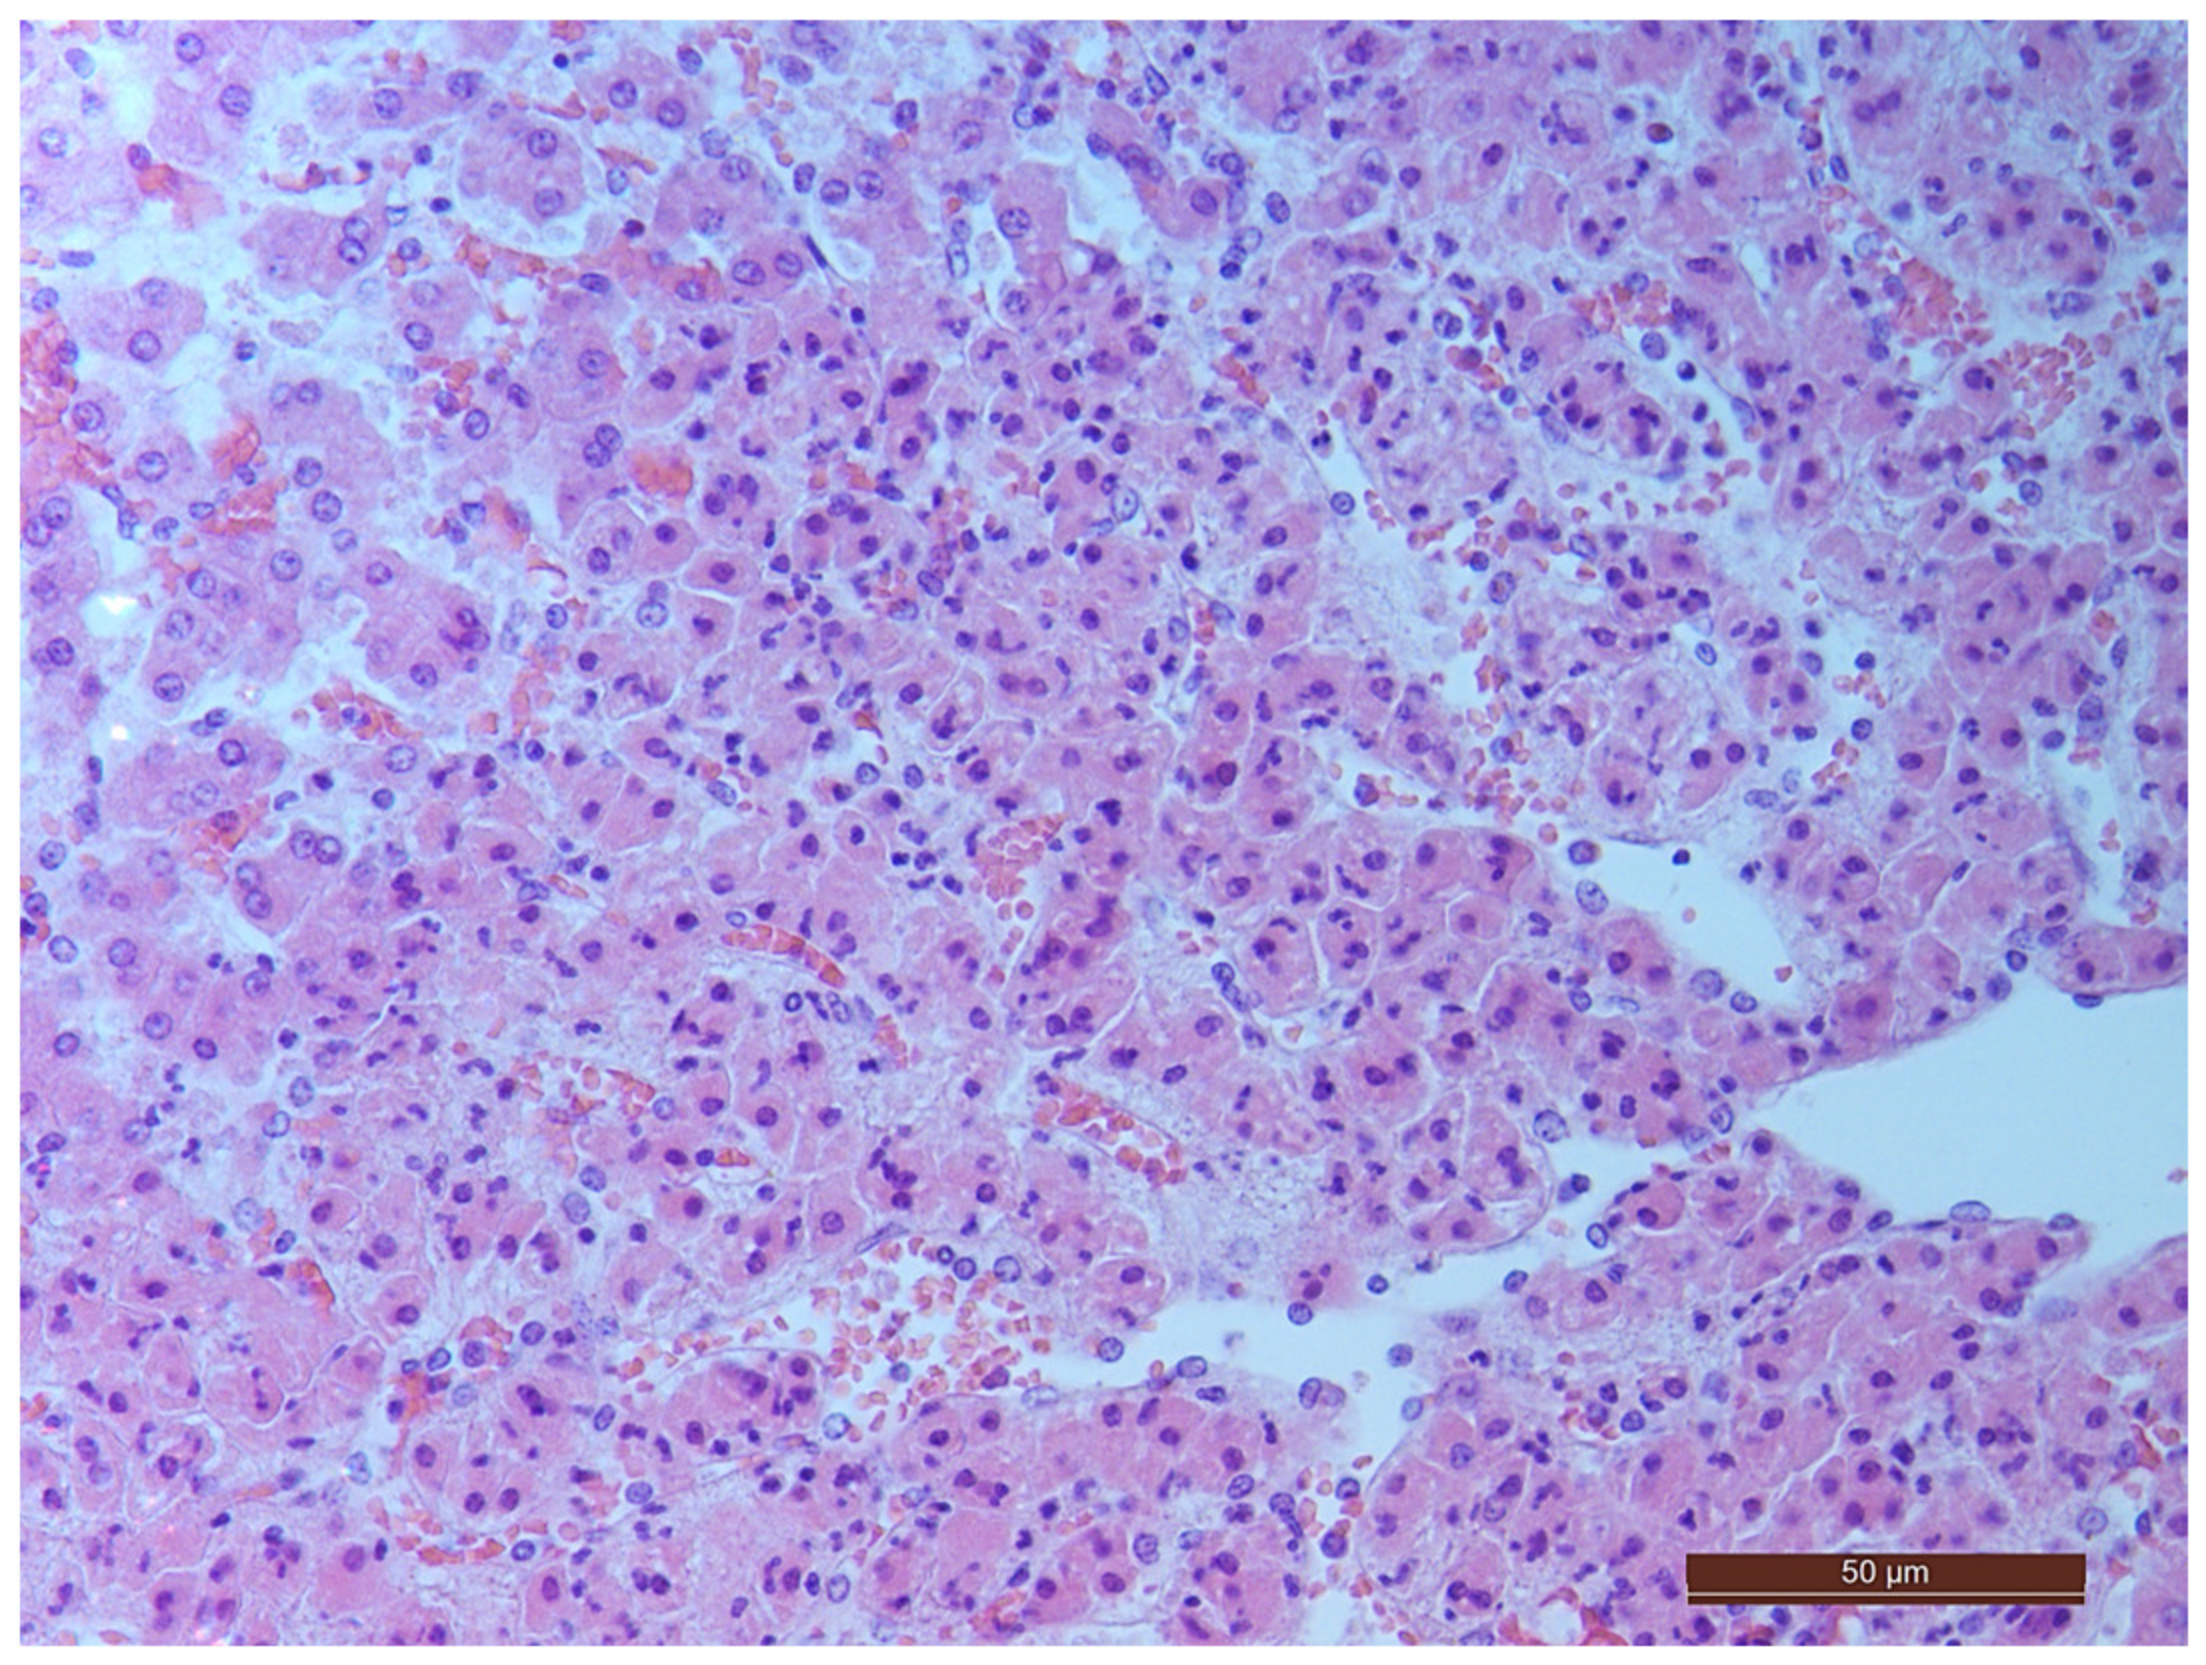

3.2. Pathology of the Liver